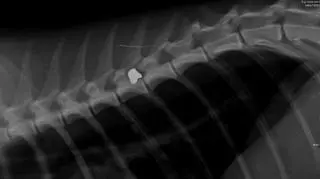

W Helu (woj. pomorskie) ktoś strzela do kotów z wiatrówki. Do tej pory zraniono już dwa zwierzaki, jednego z nich trzeba było uśpić. Na zdjęciach rentgenowskich postrzelonego kota widać śrut w okolicy kręgosłupa. Sprawę bada policja. Za znęcanie się nad zwierzętami grożą nawet 2 lata więzienia.

Pierwsze takie zgłoszenie pojawiło się 12 maja. Wówczas ktoś znalazł na ulicy umierającego kota. Trafił on do weterynarza, ale nie udało mu się już pomóc. Trzeba było go uśpić. Na zdjęciach rentgenowskich kota, widać, że został postrzelony.

Na zdjęciu widać ślady po śrucie